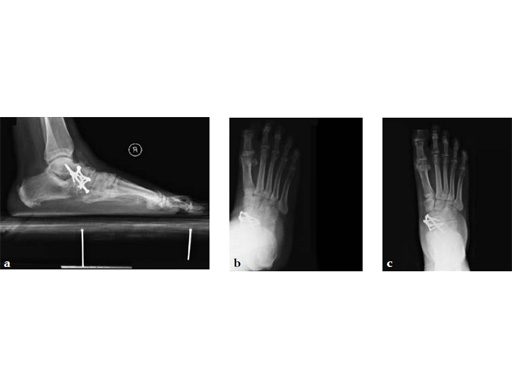

Case 3: First TMT fusion plate

A 48-year-old woman, with hallus valgus and hypermobile medial column, also resulting in pes plano abductovalgus (flatfoot).

Case provided by Andrew Sands, New York, New York, USA

Surgery consisted of first TMT and intertarsal corrective osteotomy plus fusion with movement of the first MT lateral and plantar. This corrects the hallus valgus as well as the PPAV (and stabilizes the medial column).

Case 4: First TMT fusion plate

A 60-year-old woman with pes plano abductovalgus (flatfoot deformity).

The patient was treated by headless compression screw 6.5 tuber osteotomy, TMT plantarflexing osteotomy, and first TMT fusion a plate.